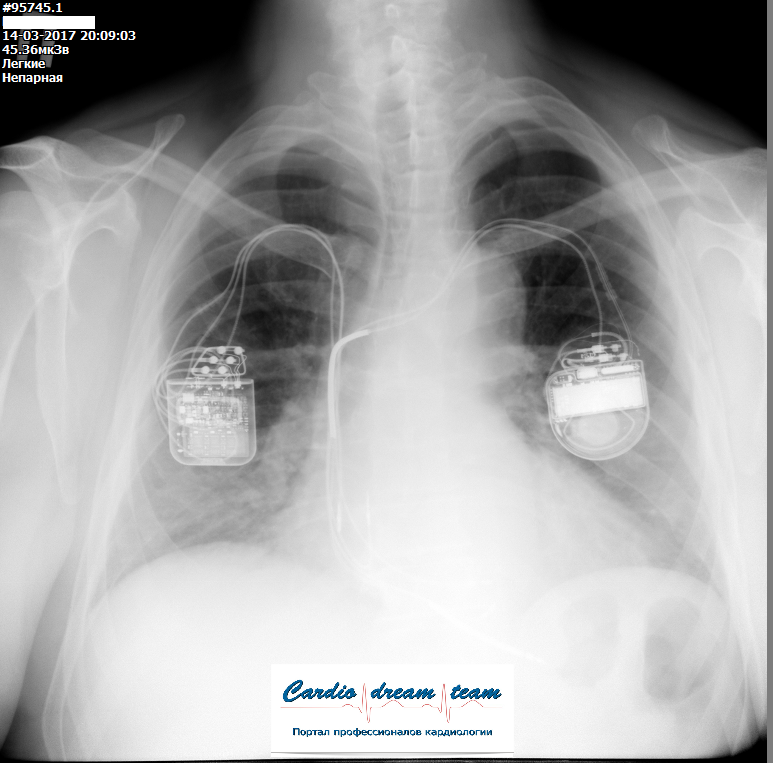

ИКД и оптимизатор у одного пациента

Обсуждалось в Госпитале Ослабленных Сердец